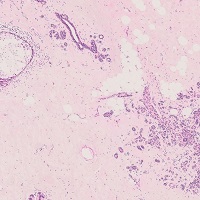

【乳腺】

良性疾患

良性腫瘍

境界悪性腫瘍

悪性腫瘍